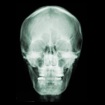

My latest Chiro-pick happens to be an original, glass “spinograph” plate from 1920.

There are many things that make this early X-ray very cool. For one thing, it came inside an envelope that stated “Palmer School of Chiropractic 1920” — meaning that this image was made only ten years after PSC introduced X-rays to Chiropractic!

The Instructor’s name on the spinograph is E.A. Thompson — the same Thompson who wrote Green Book vol 10, CHIROPRACTIC SPINOLOGY.

I am sure thousands of these spinograph plates were made; however, I am also sure there are not many of these that have survived.

The glass plate is not very transparent. The x-ray image cannot be viewed by holding it to the light of a window or overhead light.

I laid the plate on an artist’s light box where the image could be viewed. I imagine the viewing boxes at Palmer were even brighter than mine for best viewing results. The front side of the plate was smooth and shiny and could be wiped with a liquid glass cleaner. However, the back side held the image in a thin lithograph that could easily be scraped off. Naturally, I am not attempting to clean up this side for fear of rubbing off the image.

The actual radiographic picture [like the Picker’s find] was produced on glass plate, and as one might expect, the image obtained was far from the clarity we see today, not to mention relatively heavy and fragile. And while it was bound to happen anyway, the transition from glass plate to celluloid film took place, in part, because of World War I —due to the difficulty in obtaining glass from the preferred manufacturer in Belgium.

Dr. Ernest A. Thompson was the head of the Palmer School of Chiropractic Spinography Department from 1914 to 1925 and was the author of the first book on chiropractic use of x-ray — a Green Book appropriately titled Chiropractic Spinography.